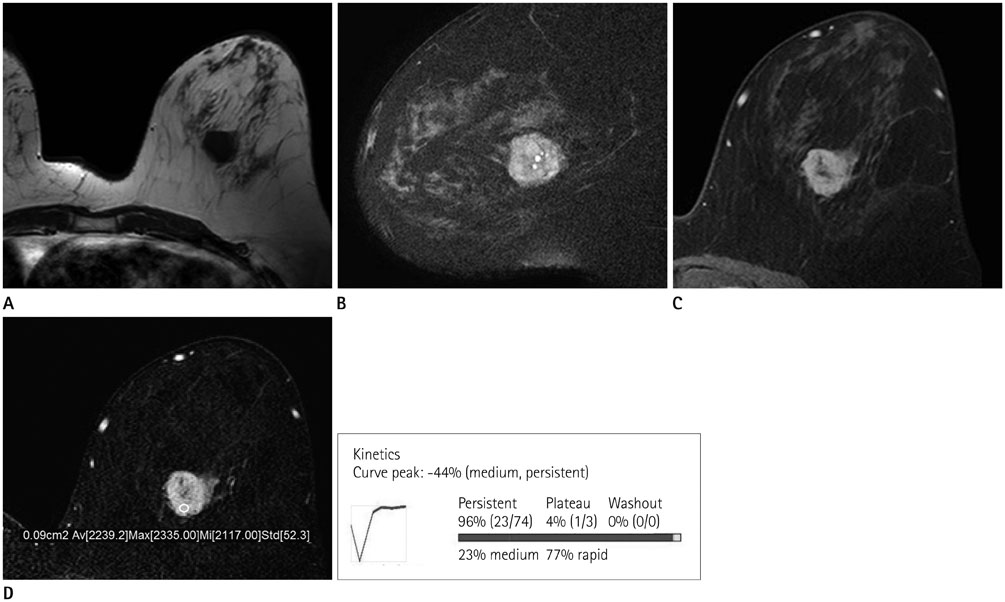

Radiologic and Pathological Correlation of Adenoid Cystic Carcinoma of the Breast: A Case Report

- Adenoid cystic carcinoma (ACC) is a subtype of adenocarcinoma that is usually seen in the salivary glands. It has also been reported in other organs including the breast, skin, tracheobronchial tree, cervix, larynx, and Bartholin gland. ACC in the breast is rare, accounting for less than 0.1% of all breast cancers. Furthermore, the imaging characteristics of ACC of the breast have not been well described in the literature, especially regarding the findings with magnetic resonance imaging (MRI). Here, we report radiologic findings of a rare case of ACC in the breast by mammography, sonography, computed tomography (CT), positron emission tomography/CT, and MRI with pathologic correlation and a review of the literature.